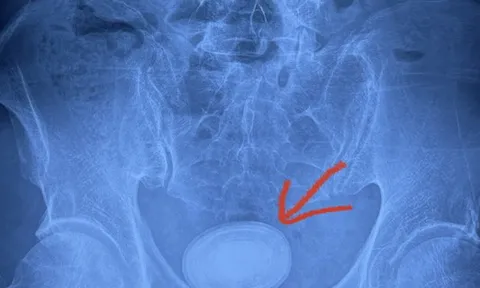

Người đàn ông có viên sỏi kích thước 6cm trong bàng quang

Trung tâm Y tế huyện Yên Lập (Phú Thọ) vừa phẫu thuật thành công trường hợp có sỏi bàng quang lớn bằng kỹ thuật tán sỏi ngược dòng.